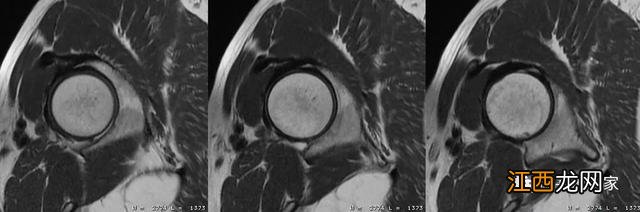

在单髋的斜冠状面和斜矢状面上定位线垂直于股骨颈可以得到单髋短轴面图像,男性髋骨x线示意图,该横断面图像是对斜矢状面和冠状面的补充 。

在单髋的横断面常采用不压脂构造的PDWI扫描 。

相位编码方向为前后方向 。

采用较短TE值,短回波链的高分辨率扫描更有利于显示髋骨关节软骨、盂唇结构 。

采用过采集技术,右侧髋骨图片,防止卷折伪影 。

FOV

160-180mm

PDWI:TE

30-40ms

层厚/间距

3.0-4.0/0-0.5mm

矩阵

≥320*224

可线根据需求合理调整相关参数 。